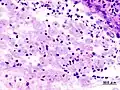

Amoebae in a colon biopsy from a case of amoebic dysentery.

Immunohistochemical staining of trophozoites (brown) using specific anti–Entamoeba histolytica macrophage migration inhibitory factor antibodies in a patient with amoebic colitis.